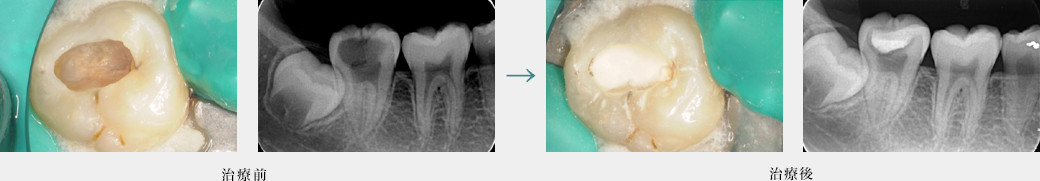

ダイレクトボンディングによる健全な歯質を温存した虫歯治療(臼歯)

健全な歯質はほとんど削らず物性に優れた樹脂を詰めています